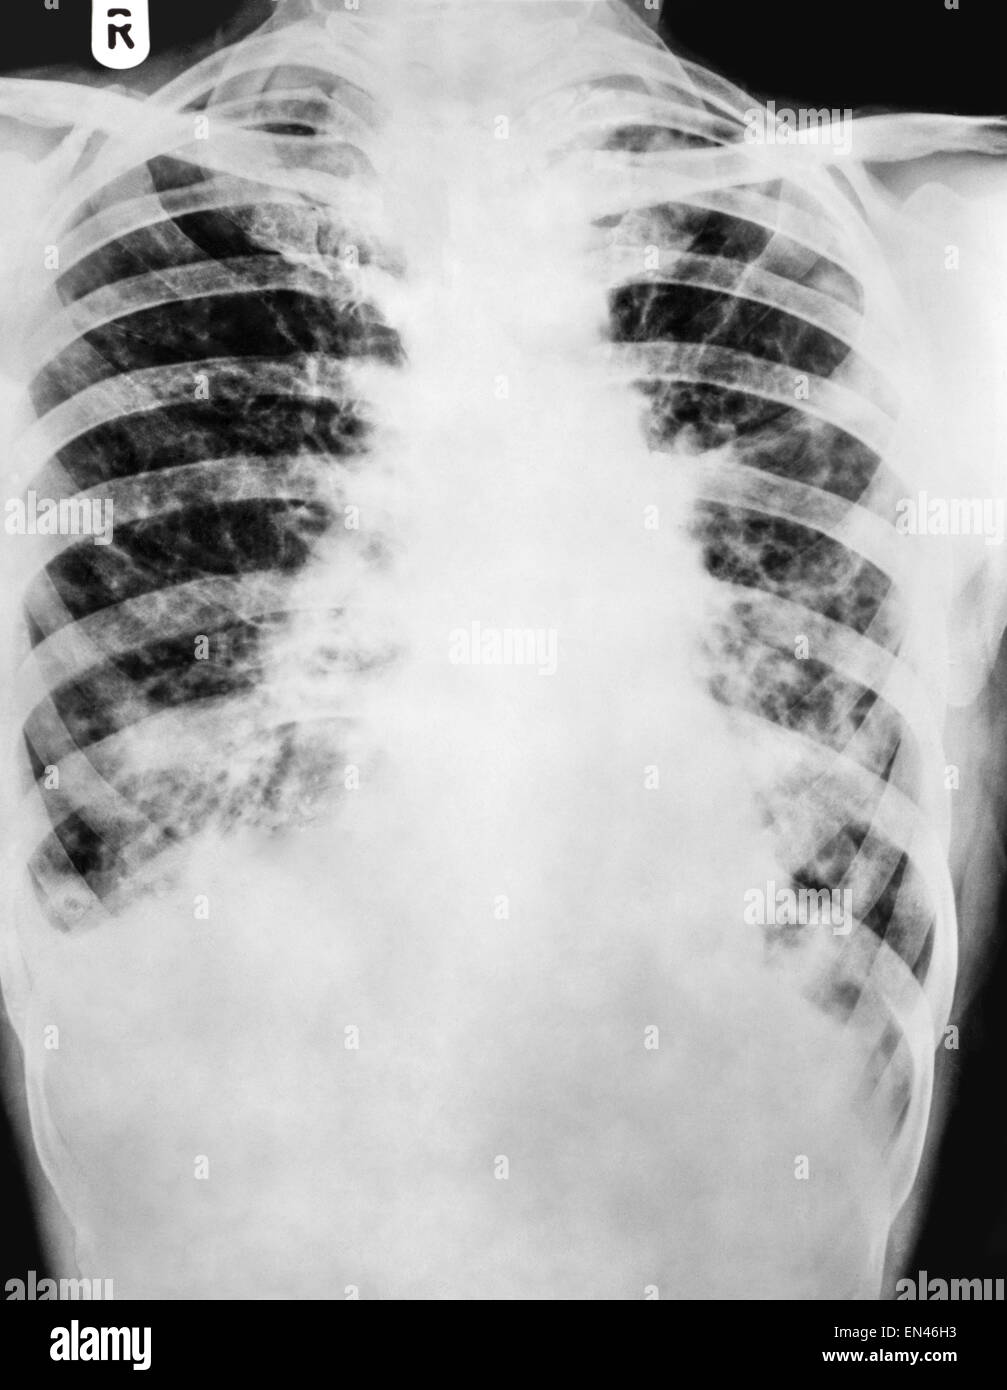

"Bronchiectasis" Xray chest show multiple lung bleb and cyst due to

"Bronchiectasis" Xray chest show multiple lung bleb and cyst due to Central Bronchiectasis Chest X Ray central bronchiectasis is typically seen in: ct chest is the investigation of choice for diagnosing bronchiectasis 1, 10 ct can identify classify bronchiectasis into. bronchiectasis is a common finding at ct, and understanding of the common and uncommon causes and their typical patterns of distribution. the location of bronchiectasis can also provide a clue as to. Central Bronchiectasis Chest X Ray.